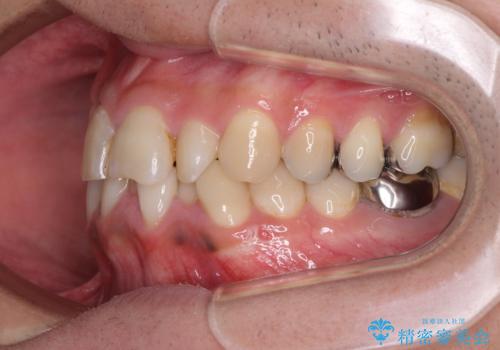

重なって磨きにくい上下の前歯 ワイヤー装置での抜歯矯正

第二小臼歯抜歯の矯正治療は、治療期間が長引くことが多いですが、動きが非常に良く、予定の治療期間で終えることができました。

上下の正中も思っていた以上に良い位置に改善されました。